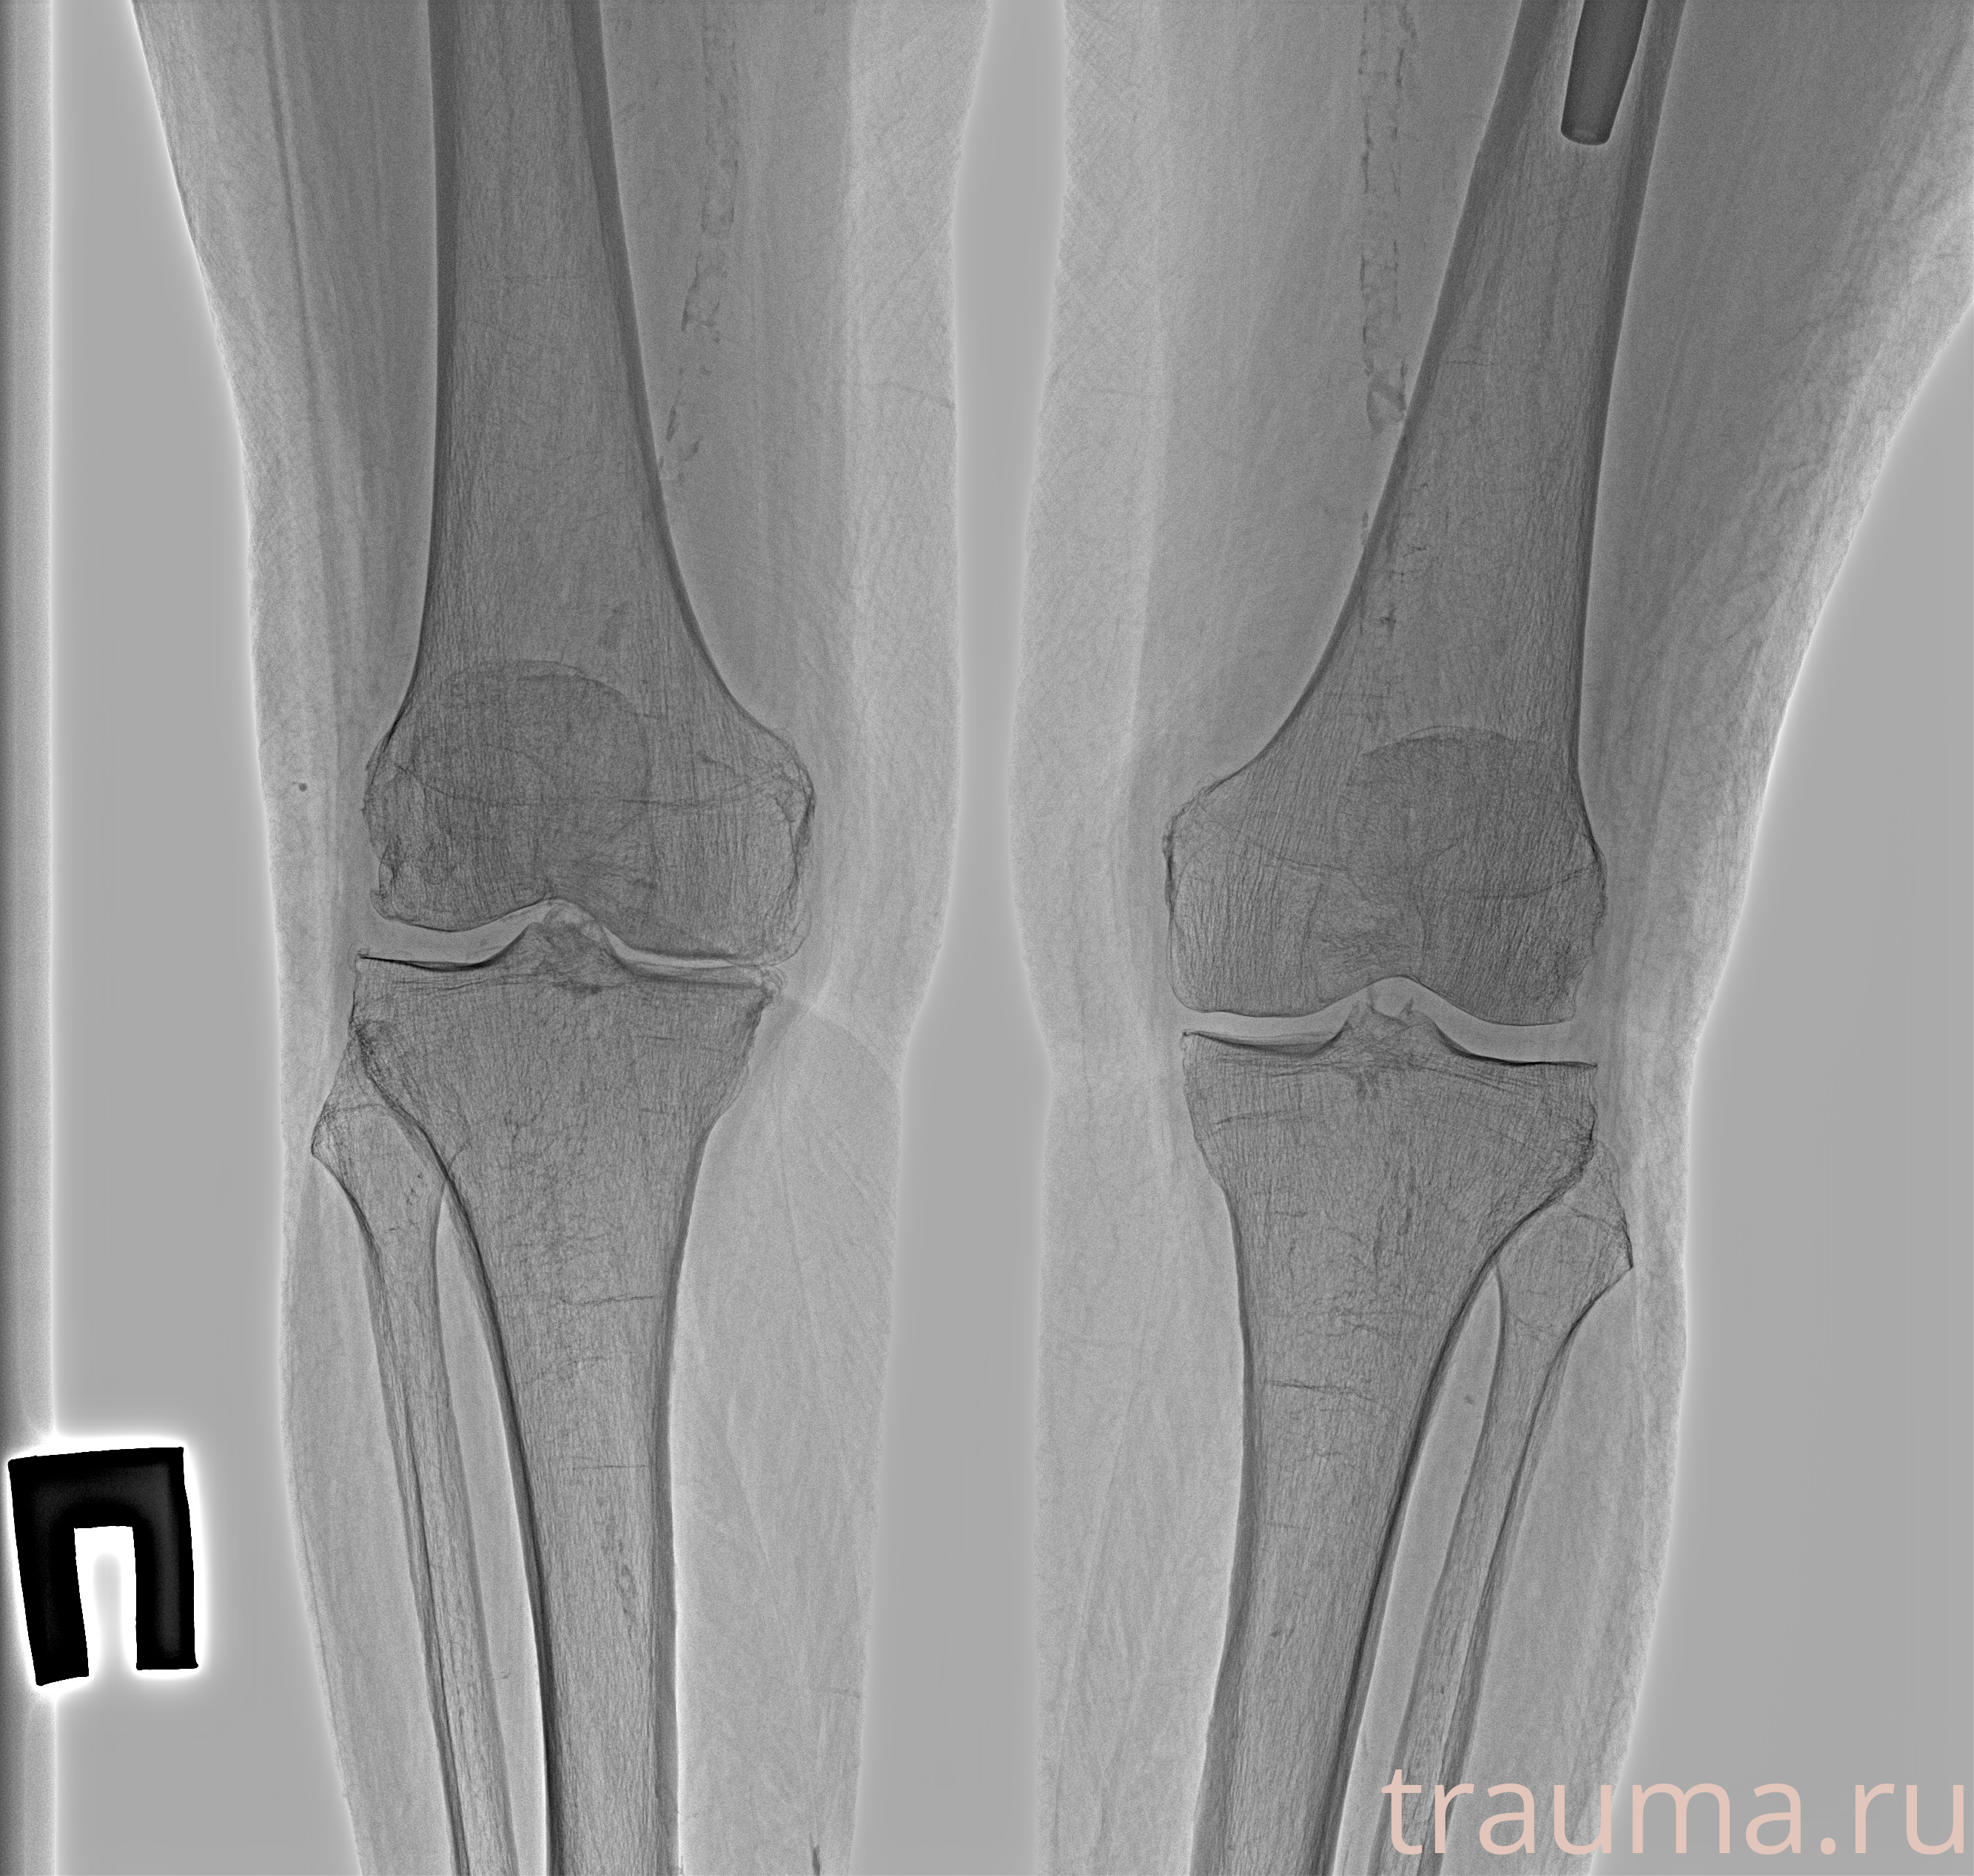

Рентген на дому: по вашему адресу приезжает врач-рентгенолог, травматолог-ортопед с мобильным рентгеновским аппаратом, проводит диагностику травмы или заболевания, делает необходимые рентгенограммы, дает рекомендации по дальнейшему лечению. Получить качественные снимки в домашних условиях возможно благодаря уникальной методике, разработанной МосРентген Центром для института  Склифосовского